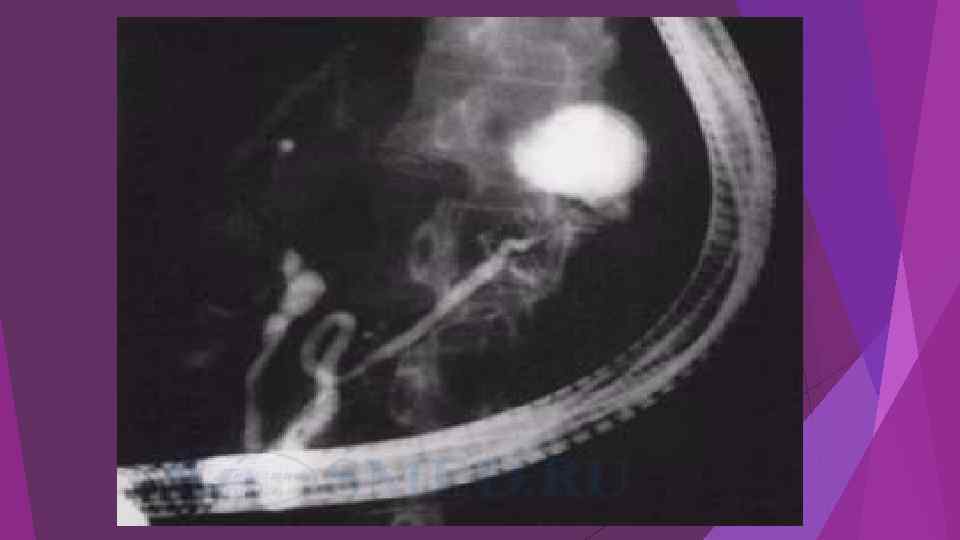

Острая блокада терминального отдела холедоха (острый панкреатит)

Острая блокада терминального отдела холедоха (острый панкреатит)